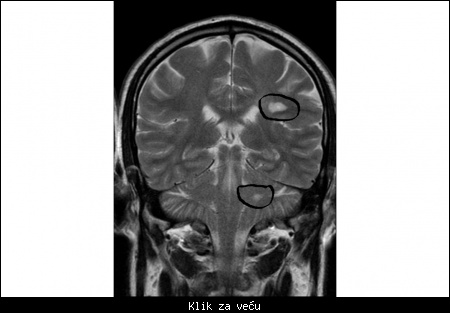

MRI snimak iz licne kolekcije.

Slika pokazuje dve demijelizacione lezije karakteristicne za MS, u dva razlicita dela nervnog sistema.